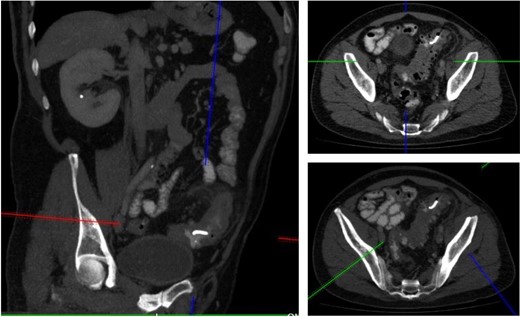

A 52-year male was referred to the surgical team for a 1-day history of left iliac fossa pain accompanied by nausea and the inability to open his bowels for 48 hours. The pain was 9/10 in severity, sharp, persistent and with a gradual worsening onset. The patient was previously diagnosed with extensive diverticular disease and admitted 2 months prior with acute sigmoid diverticulitis. 18 months earlier he underwent an emergent laparoscopy for an unclear pelvic inflammatory mass on CT, that suggested either severe sigmoid diverticulitis or appendicitis. He also had multiple polyps throughout the colon, that were endoscopically removed. The patients past medical history was significant for a non-flow limiting coronary artery disease, arterial hypertension and an allergy to penicillin and tetracycline. Temperature on admission was 38.7 C, blood pressure of 149/109 mm/Hg, pulse of 109 bpm and a respiratory rate of 20/min with O2-saturations of 96% on room air. The abdomen was soft with tenderness and guarding over the left iliac fossa. Bowel sounds were present. Investigations showed a white cell count of 17.6 tsd/ul and a CRP of 64 mg/l. No pneumoperitoneum was detected on an erect chest x-ray. Treatment with ciprofloxacin and metronidazole was started and the patient kept nil per mouth. CT imaging showed extensive sigmoid diverticular disease with marked pericolonic fat stranding and free gas tracking into the mesenteric fat. Gentamycin was added and within 3 days the patient’s clinical symptoms improved. He was apyrexic and the white cell count dropped to 10.9 tsd/ul. A repeat CT scan showed a stable appearing localized perforation with reduced free gas and no signs of collection. However, of note was a small curvilinear metallic foreign body within the lumen of the sigmoid colon of uncertain etiology (Fig. 1). On questioning, the patient recalled a mechanical fall with a head contusion 9 days prior to admission during which he lost his partial denture. The patient was commenced on laxatives and despite bowel movement on the following day, the foreign body did not pass. A PFA showed the persistent presence of the metallic foreign body over the sigmoid colon, which raised the suspicion of impaction (Fig. 2). The patient was prepared for colonoscopy and the foreign body was identified impacting the lumen of the sigmoid colon (Fig. 3). However, endoscopic retrieval failed and the decision was made to proceed with laparoscopic anterior resection. Intraoperative findings showed a rigid and thickened sigmoid colon with adhesions and a diverticular abscess. About 22 cm of sigmoid colon was resected and the procedure was completed with a primary colo-rectal end to end anastomosis, using a 31 mm CEEA-Stapler. The resected sigmoid colon contained the lost partial denture, which showed impaction and perforation into the sigmoid mesocolon (Fig. 4). Following surgery, the patient was transferred to the surgical ICU for 24 h observation and discharged home after one week.

CT imaging identified a small curvilinear metallic foreign body within the sigmoid colon.